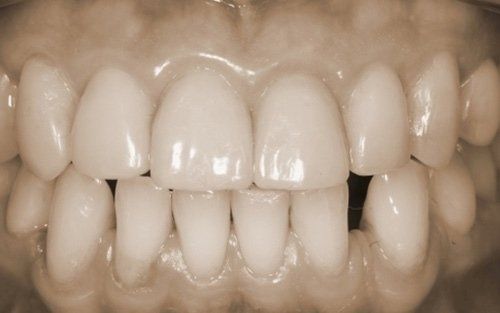

The constant presence of acidic substances causes the gradual loss of the hard tissues of the tooth

and the consequent modification of both the aesthetics of the tooth and its dimensions. The patient often begins to stop smiling, ashamed of the appearance their teeth have taken, in addition to frequently experiencing dental sensitivity that develops proportionally to the progression of the process. Sometimes this phenomenon is associated with